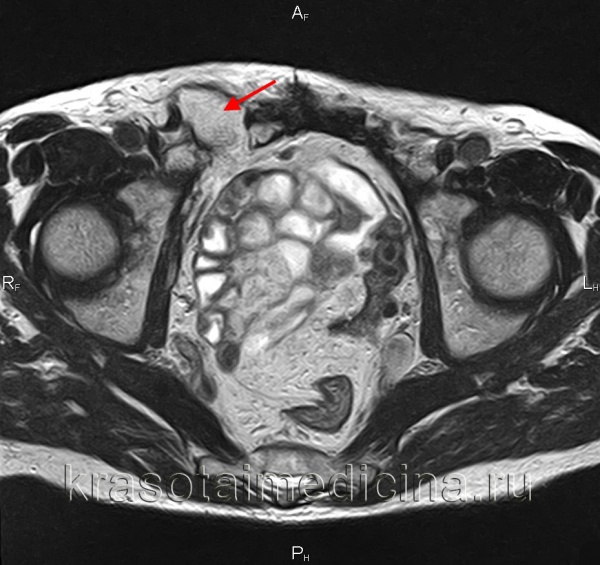

(Правый) У этого же пациента при КТ с контрастным усилением, выполненной по поводу травмы нижней конечности, на аксиальной томограмме определяется косая паховая грыжа, содержащая жировую клетчатку. Грыжа не вызывала жалоб. (Левый) На рисунке изображена паховая грыжа. Обратите внимание, что шейка бедренной грыжи локализуется медиальнее общей бедренной вены и ниже паховой связки.